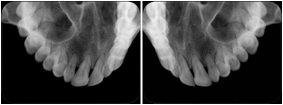

OO.1.2 Ophthalmology

1. A patient in rural Canada visits a general ophthalmologist and is found to have diabetic macular edema. The general ophthalmologist would like to discuss the case with a retina specialist before performing laser surgery. A fluorescein angiogram is done with multiple retinal images taken in a timed series after an intravenous injection. The images along with a Structured Display are shared via a Health Information Exchange with a retina specialist in Calgary, who opens them using his Ophthalmology EMR software and consults via phone with the general ophthalmologist. Both physicians view the images in the same layout so the retina specialist can provide accurate guidance for treating the patient.

2. A patient in rural Iowa visits his primary care physician for management of diabetes. Three non-mydriatic (patient's eyes are not dilated) photographs are taken of the back of each eye, and forwarded electronically along with a Structured Display to an ophthalmologist in Iowa City. The ophthalmologist reads the photos in an agreed upon layout so there is no mistake about what portion of which eye is being viewed. The ophthalmologist is able to tell the primary care physician that his patient does not need to come to Iowa City for face to face ophthalmologic care, but that there is a particular view of the left eye that should be photographed again in 6 months.

Ophthalmic Retinal Study Structured Display

Figure OO-3. Ophthalmic Retinal Study Structured Display